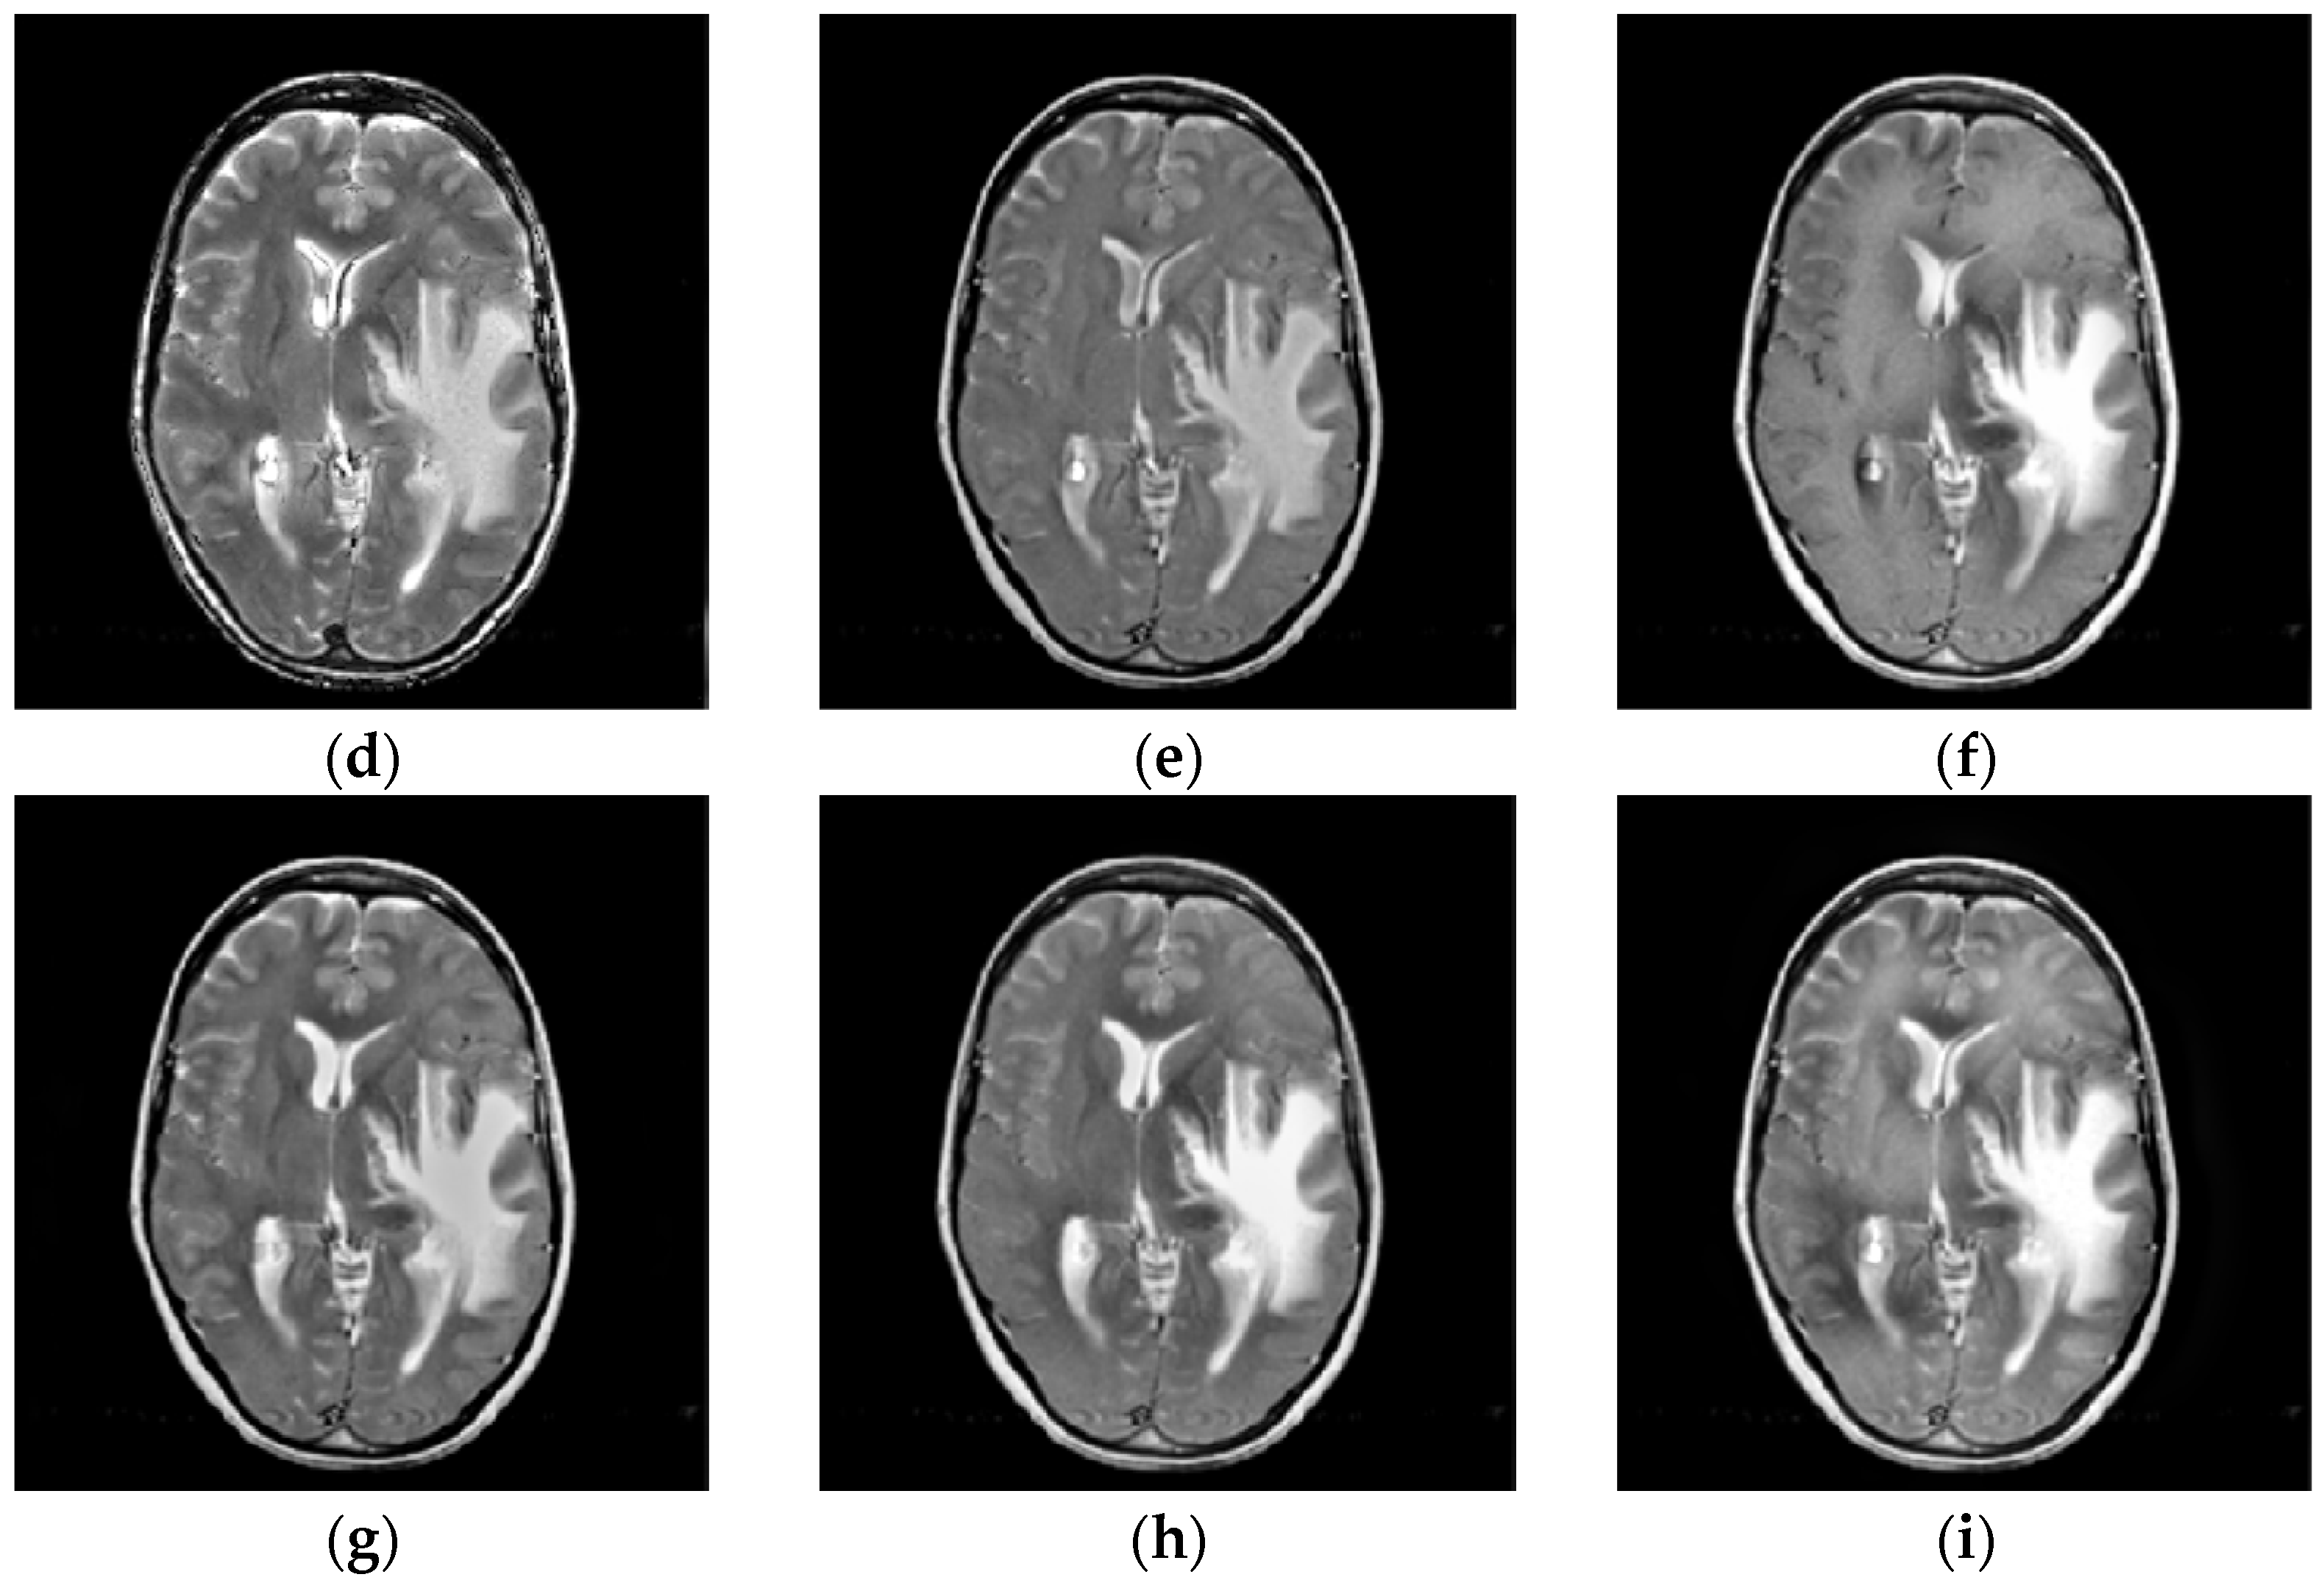

4.2. Comparison of Gray Image Fusion